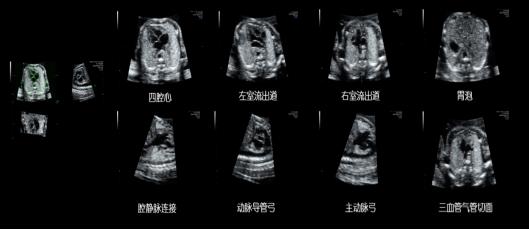

梦想系列煊光E8先进的探头技术、高品质的基础图像、以及一整套先进的胎儿心脏成像技术来评估胎儿心脏结构和功能,基于革命性的腔内探头技术,将早孕期胎儿心脏检查带入前所未有的水平,分析方法和流程包括:高级STIC (时间空间相关成像) 包括SonoVCAD heart新优势 (胎儿心脏计算机辅助诊断)和STIC M型技术,高级STIC结合B-Flow成像,Z-Score 评价胎儿心脏结构生长的定量工具,包括评估先天性胎儿心脏异常的定量分析,用于高质量的胎儿心脏专项检查。